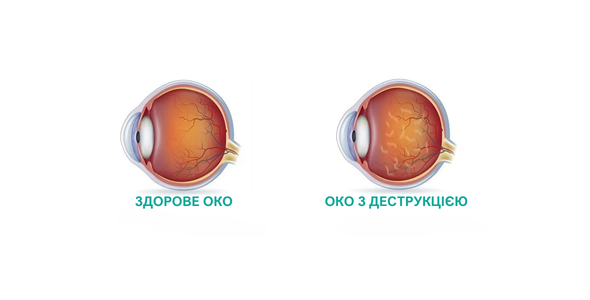

Діабетична ретинопатія — це ускладнення діабету, яке вражає сітківку ока (шар тканини, що вистилає внутрішню частину ока і відповідає за сприйняття світла).

Екструзія силікону — це ускладнення, яке може виникнути після введення силіконової олії в око для лікування певних офтальмологічних захворювань, таких як відшарування сітківки. У випадках, коли екструзія значна або викликає серйозні ускладнення, може знадобитися повторна операція для видалення силіконової олії або зміцнення оболонок ока. Іноді проводять процедуру знову, замінюючи силікон іншими матеріалами або коригуючи його кількість.

Операція з приводу відшарування сітківки — це хірургічне втручання, спрямоване на відновлення нормального положення сітківки на задній стінці ока. Відшарування сітківки є серйозним офтальмологічним захворюванням, яке може призвести до втрати зору, якщо його не лікувати.